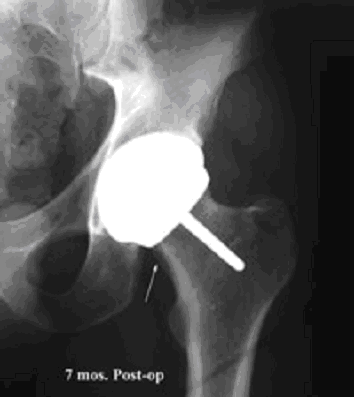

Sistema novedoso de revestimiento de cadera ayuda a preservar el hueso

Un nuevo sistema de revestimiento de cadera está diseñado para ofrecer alivio del dolor y restablecimiento de la función, mientras que retiene tanto hueso sano como es posible y conserva opciones de cirugía futuras, incluyendo un reemplazo total primario de cadera. Más...08 Feb 2010